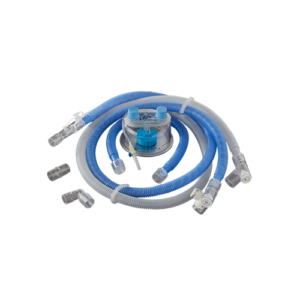

BC 630

Adult Breathing Circuit with Heated Wire for High Flow Oxygen Therapy